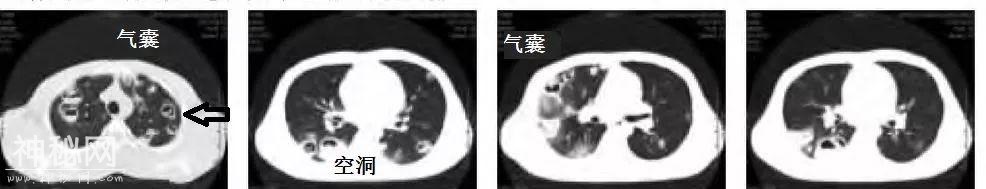

患者女性,巴氏腺脓肿切开,一天后发热,症状逐渐恶化,高热,咳嗽,气促。

教你从肺CT上分辨是哪种细菌感染丨葡萄球菌肺炎篇-7.jpg

教你从肺CT上分辨是哪种细菌感染丨葡萄球菌肺炎篇-8.jpg

教你从肺CT上分辨是哪种细菌感染丨葡萄球菌肺炎篇-9.jpg

多发气囊、结节、空洞,胸膜下为主。加之脓肿切开术后。妥妥的金葡菌肺炎。